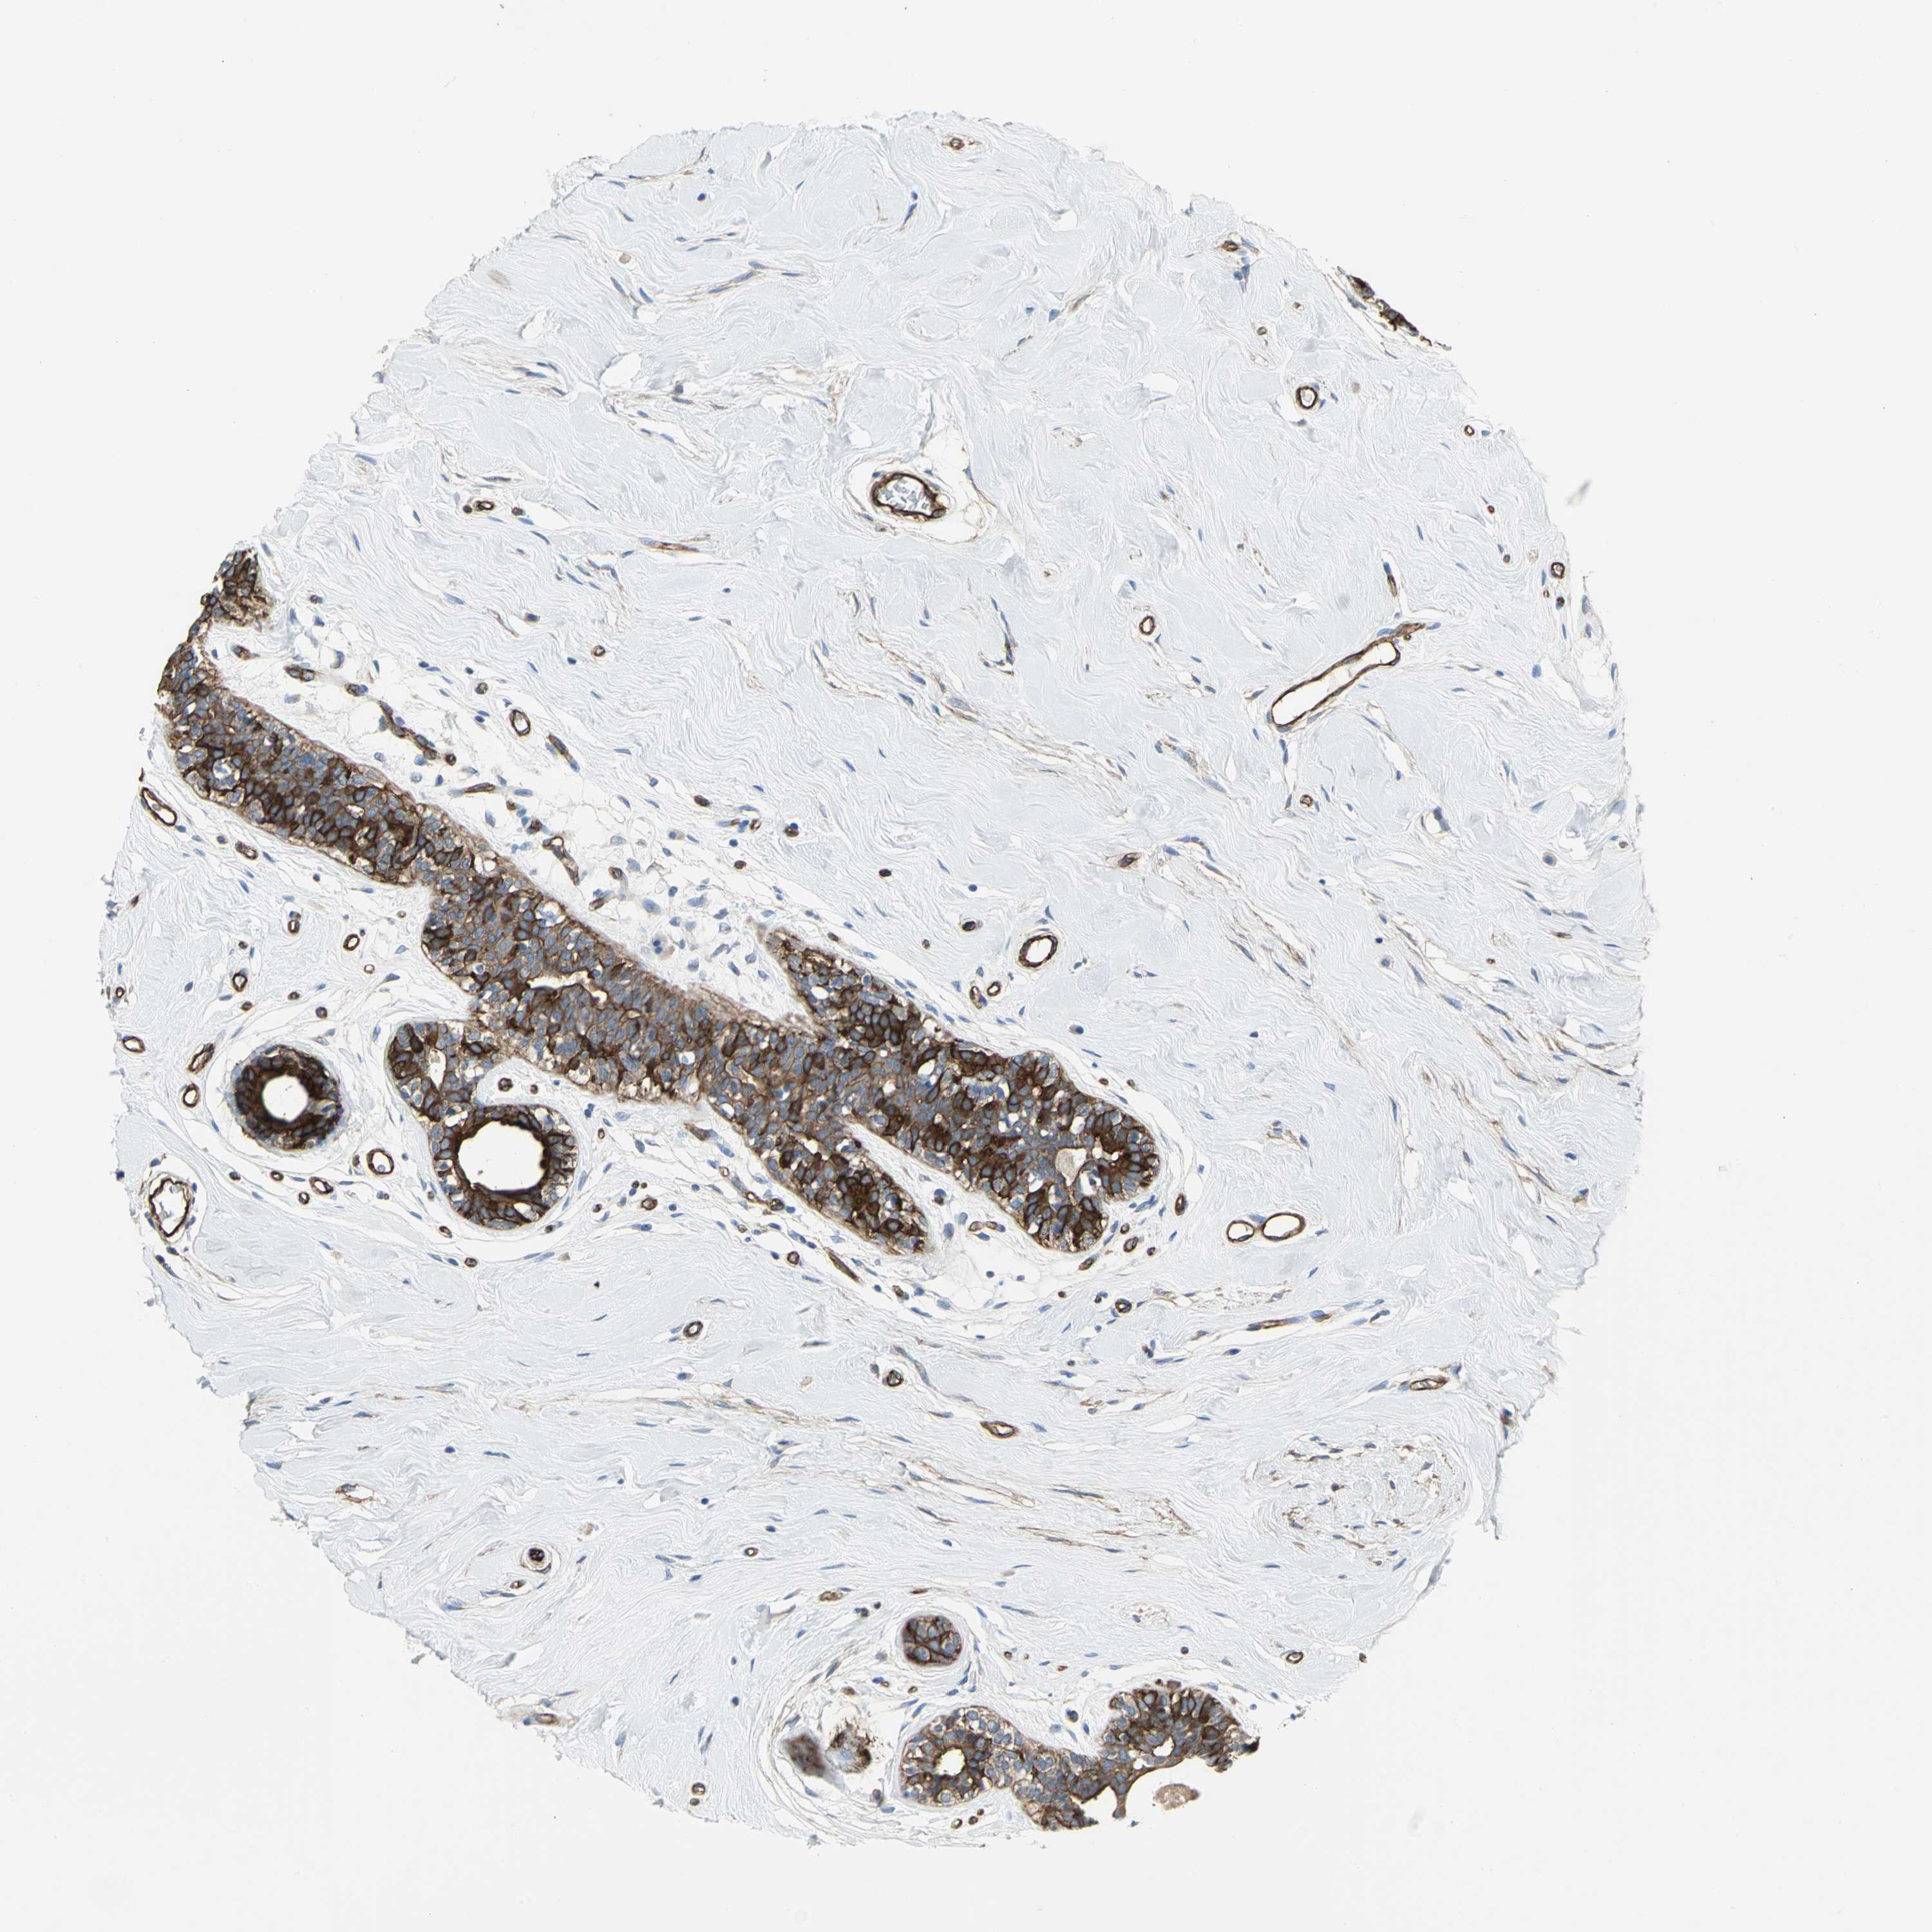

BRCA TCGA BRCA VALIDATION PROTEIN EXPRESSION